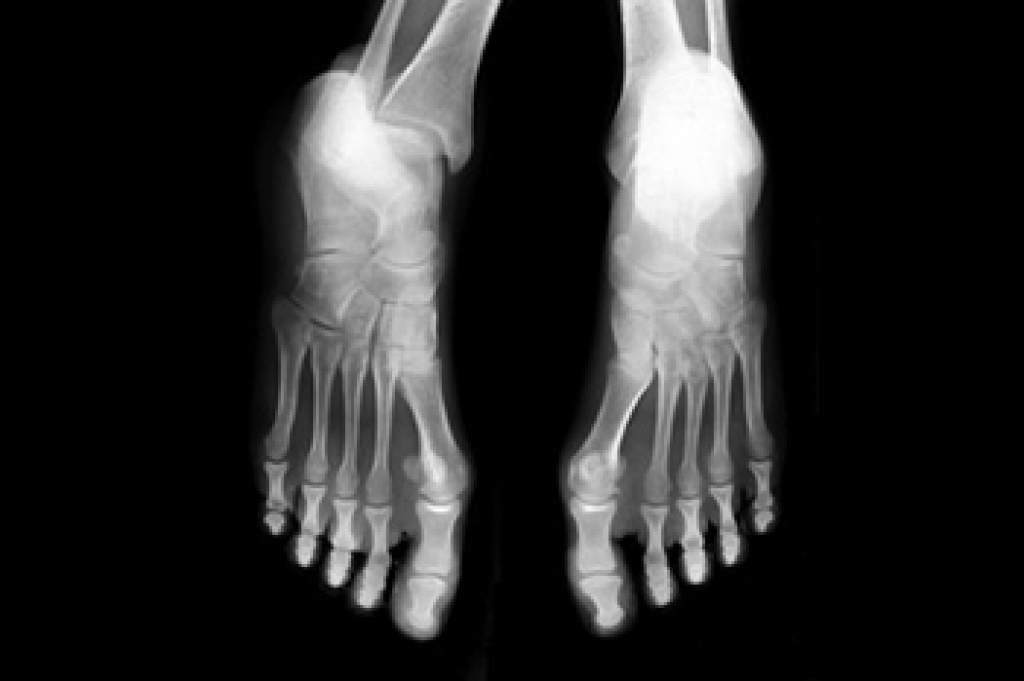

To figure out the cause of foot pain, podiatrists utilize several different methods. This can range from simple visual inspections and sensation tests to X-rays and MRI scans. Prior medical history, family medical history, and any recent physical traumatic events will all be taken into consideration for a proper diagnosis.